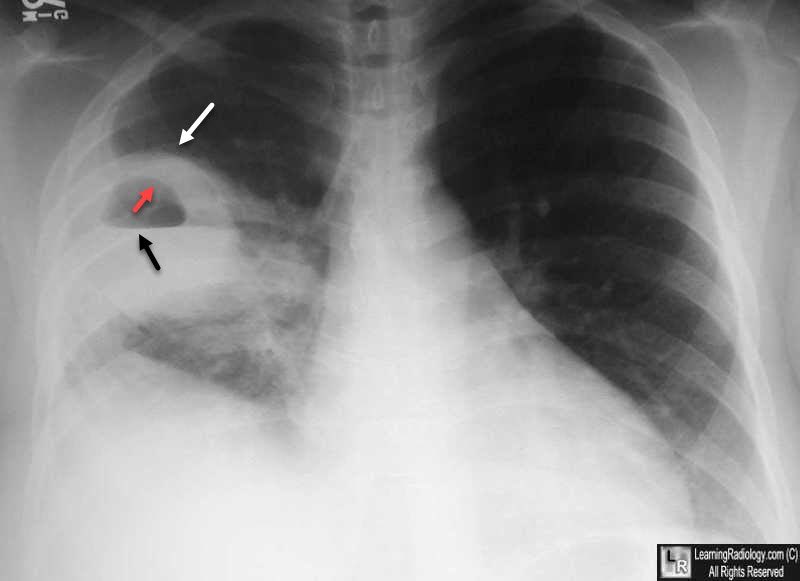

السؤالين ذي دايم اشوفها بشكل متكرر في بنوك الاسالة: ١) وش ال screening اللي يتسوى في المدخنين "فقط" (عشان اسهلها، هم ٢ مهمين) ٢) على اي عمر نبدا ونوقف لكل واحد ؟ "As per USPSTF”